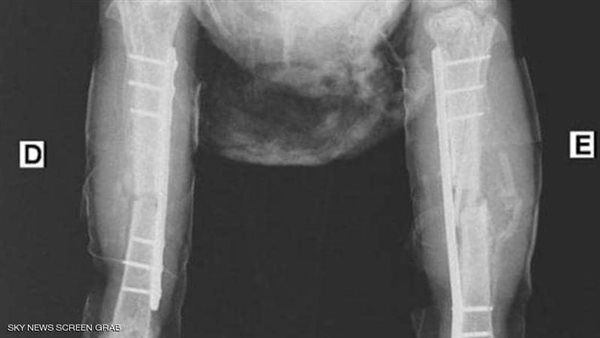

وأكد جوليو أرودا، طبيب بيطري برازيلي، على صفحته الشخصية، بإنه هو الطبيب المعالج للدجاجة، وقد أجرى لها العمليتين لإصلاح كسور تعرضت لها،  بسبب سوء المعاملة والتعذيب، واستخدامها أيضًا في طقوس دينية لمعتقد غير معروف.

ونشر الطبيب البرازيلي عددًا من الصور للدجاجة بعد تضميد قدميها فضلاً عن الفحوصات الخاصة بحالتها الصحية، لتوضيح مدى صعوبة العمليات التي أجراها.

وتابع أرودا: "أجريت العملية الأولى للدجاجة في 2 سبتمبر الجاري، ثم عملية ثانية بعدها بيومين، لوضع "شرائح مسامير" لمعالجة الكسور الموجودة، وهي الآن في حالة مستقرة، لكن عملية الشفاء تحتاج إلى مزيد من الوقت.